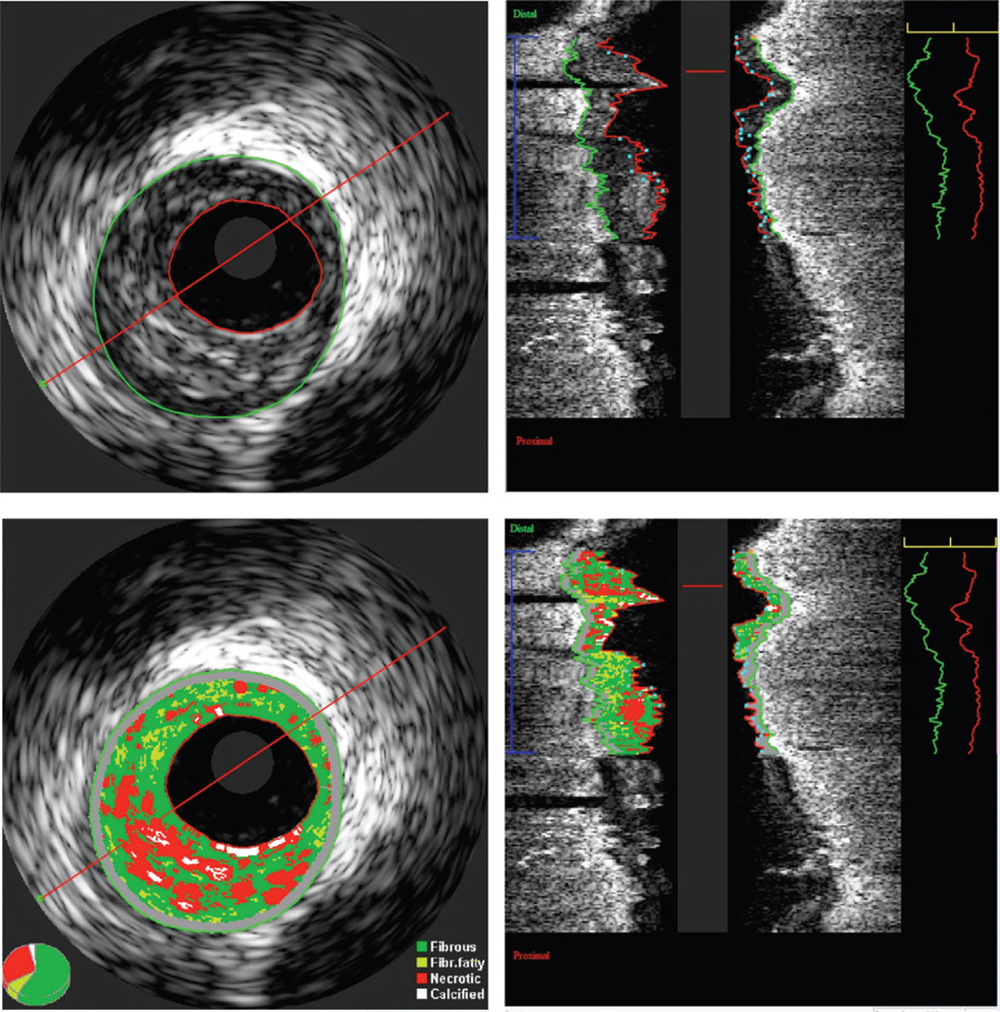

Figure 1. Information theoretic quantification of the absolute plaque volume. Grayscale intravascular ultrasound (IVUS) image (top). Virtual histology IVUS image (bottom). A region of interest is defined and analyzed by indicating the outlines of the lumen and the external elastic membrane in all frames. Out of this analysis, lumen, vessel, and plaque volumes are calculated together with virtual histology data such as fibrofatty and fibrous plaque volumes. Image courtesy of Jurgen M.R. Ligthart, BSc.

The pathophysiology of no-reflow is likely multifactorial; the type of plaque may be an important predictor for no-reflow after PCI. A few observational studies have reported that the angiographic no-reflow phenomenon is associated with atherosclerotic plaque characteristics detected by intravascular ultrasound (IVUS) before PCI in acute MI patients,6,7 however, with inconsistent results.8-16 Because of the small sample size, the power achieved in those studies was not sufficient to detect whether coronary plaque composition increased risk of no-reflow after PCI (Figure 1). Using all available published data to increase statistical power, meta-analysis is an efficient way of analytically combining the results of individual studies together to detect and quantify an effect with more precision.